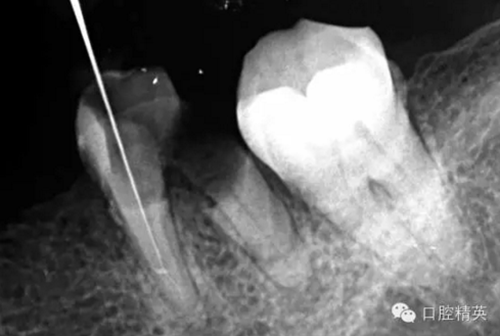

近頰為疏通。慢慢找點(diǎn)可下,近頰花費(fèi)一小時(shí)。